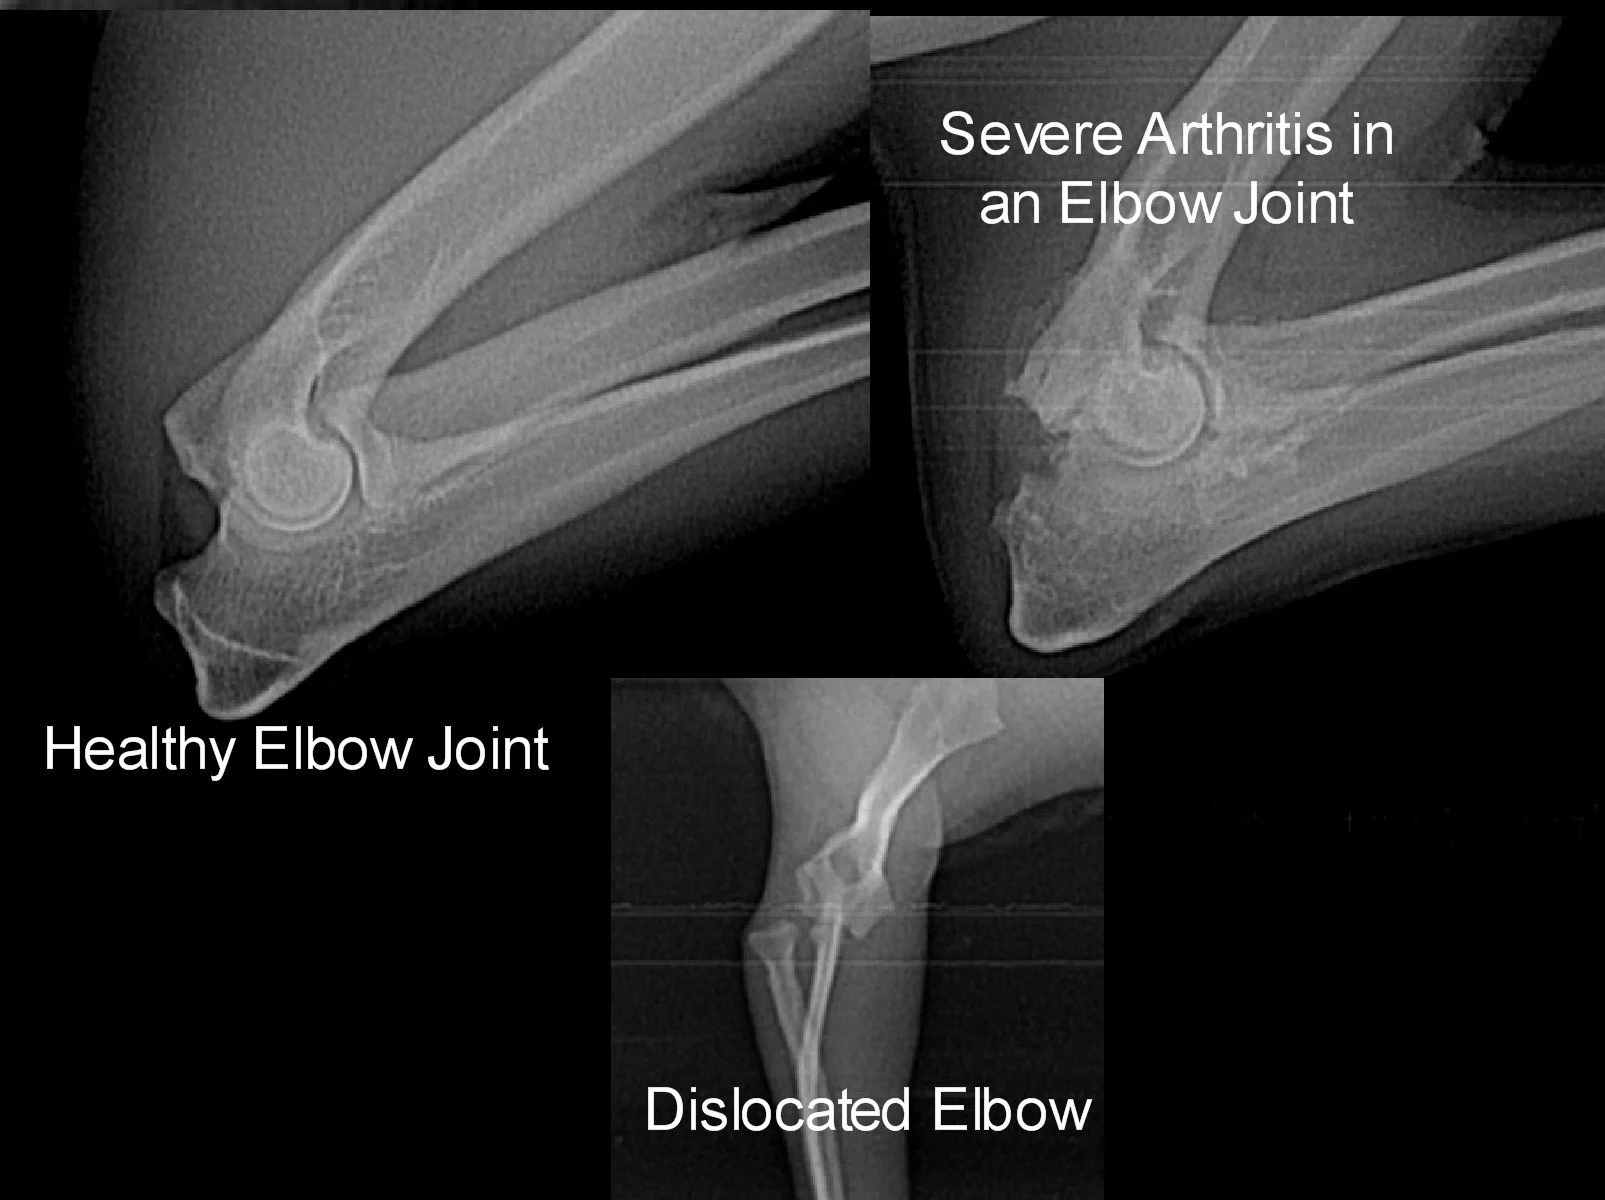

Examples